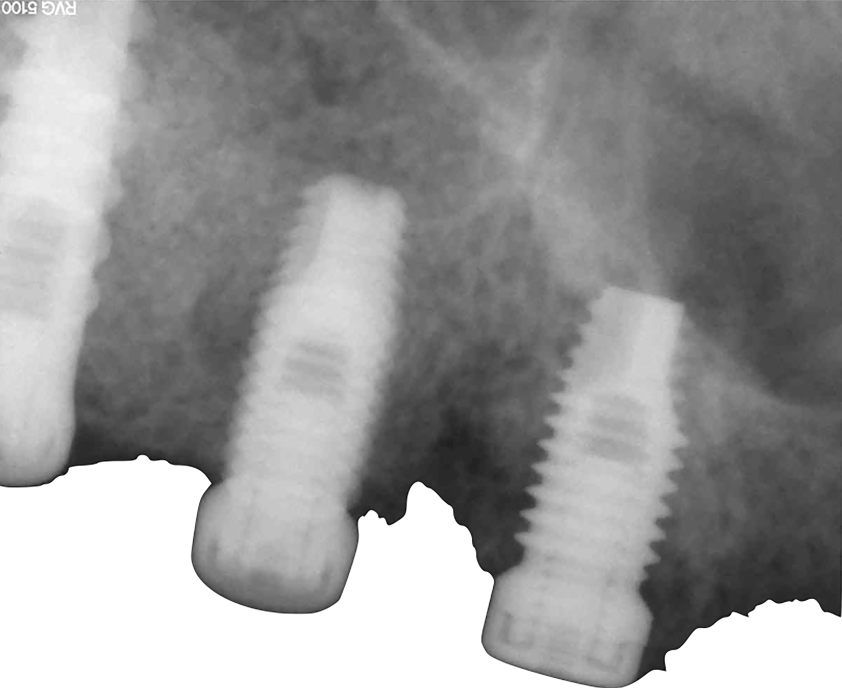

Un paziente maschio di 58 anni (Fig. 1), senza anamnesi medica rilevante, si presenta alla nostra attenzione richiedendo una riabilitazione protesica fissa su impianti alle due arcate. L’edentulia e l’atrofia ossea all’arcata superiore, come verosimile risultato di parodontite cronica dell’adulto, e la presenza di tre denti e due impianti con una prognosi parodontale infausta, sono evidenti all’esame clinico e nelle immagini radiologiche (Fig. 2), così com’è visibile l’incongruenza delle protesi rimovibili, con estetica compromessa e malocclusione in cross bite monolaterale (Fig. 3), con segni e sintomi disfunzionali.